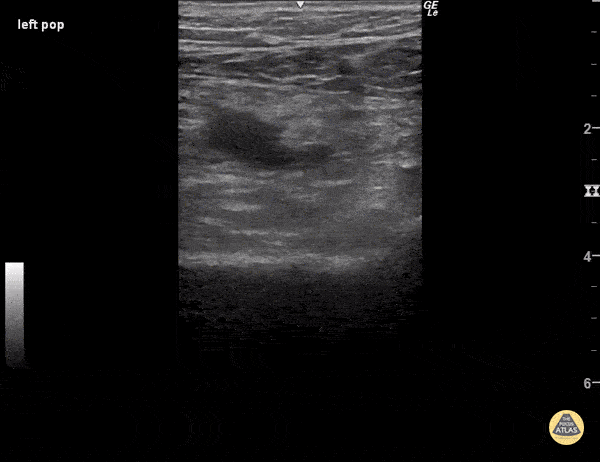

When pressure is applied to the ultrasound probe over blood vessels, veins usually collapse before arteries because of their much thinner walls. In this clip, enough pressure was applied to the ultrasound probe to partially collapse the popliteal artery, which is the pulsatile vessel visualized. Despite such high pressure, the popliteal vein remains fully patent, indicating a deep vein thrombosis within its walls. Sukh Singh, MD